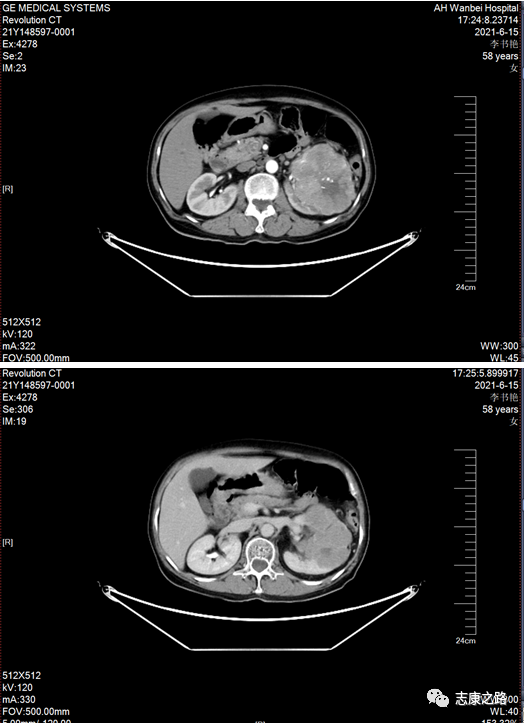

近日皖北总院泌尿外科团队成功为2名肾癌患者实施手术治疗。此2名患者为其中一名为中年男性,一名为老年女性,皆因体检发现肾占位入住皖北总院泌尿外科,入院后完善相关检查。

(术前CT检查)

其中一名患者术前影像学检查提示肾癌直径大于10公分;另一名患者肾癌直径大于7公分,均属于巨大肾癌,因体积巨大,后腹腔操作空间狭小,手术难度较大。经过科内的充分讨论分析及与病理科科、影像科等相关科室多学科联合会诊,制定了详细的治疗方案及手术风险的解决措施,各专科主任各抒己见,这2名患者需手术治疗,考虑肾癌的可能性较大。科主任李虎指出:患者肾癌体积较大,手术难度较大,术前充分与患者沟通手术风险,拟对此2名患者实施腹腔镜下肾根治性切除术。